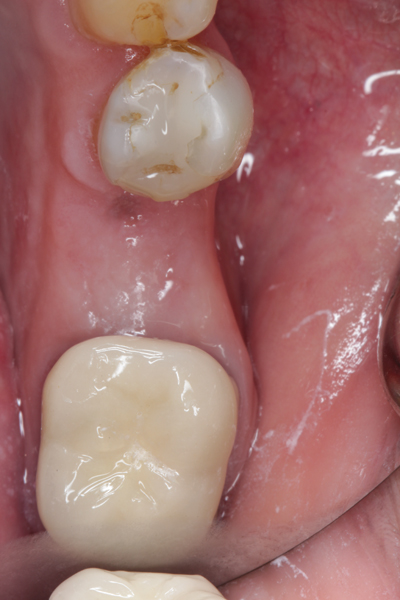

Fig 1. (Case 1) Tooth No. 19 manifested a buccal fistulous tract. Probing depth on the buccal was 8 mm.

Figure 1